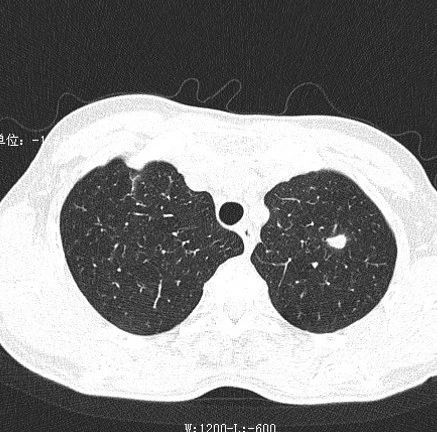

主因咳嗽1周,无发热——周围型肺癌 影领学苑 · 公众号 · · 5 年前 · |

【收藏】肺部常见疾病影像诊断学口诀 影领学苑 · 公众号 · · 5 年前 · |

肺部空洞病灶的影像诊断 影领学苑 · 公众号 · · 5 年前 · |

间断咳嗽3年——机化性肺炎 影领学苑 · 公众号 · · 5 年前 · |